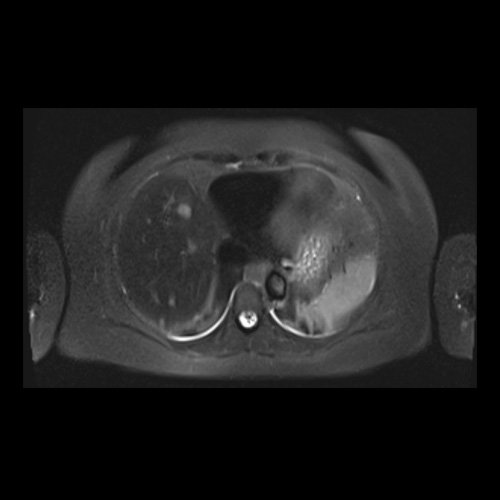

RMN de abdomen con contraste endovenoso (14/02/26)  Corte axial (T2): múltiples lesiones sólidas de distribución difusa, levemente hiperintensas.

• RMI abdomen y pelvis con contraste EV (14/02/26): En las bases pulmonares se visualizan atelectasias laminares bibalsales. No se identifica derrame pleural. El hígado es de forma, tamaño y situación normal. La superficie es lisa, los bordes son agudos. Se observan múltiples lesiones sólidas de distribución difusa, levemente hiperintensas en T2, con restricción en difusión y realce homogéneo tras la administración de contraste EV, la de mayor tamaño de 15 mm en segmento VII. Sugiero conocimiento histológico. La vía biliar intra y extrahepática es de calibre conservado. La vesícula biliar es de forma y situación habitual, sus paredes son finas y no presenta imágenes hipointensas en su interior, que sugieran la presencia de litiasis. El bazo es de forma, tamaño y situación normal, sin efectos de masa focales. El páncreas es de forma, tamaño y situación normal, sin efectos de masa. El Wirsung es de calibre conservado. Glándulas adrenales de forma, tamaño y situación normal, sin efectos de masa. Ambos riñones son de forma, tamaño y situación normal, con adecuada diferenciación córtico subcortical. No se observan alteraciones a nivel de la vía excretora. No se observan adenomegalias retroperitoneales ni intraperitoneales. La aorta abdominal, las arterias iliacas primițivas, internas, externas y femorales son de trayecto y calibre normal La vena cava inferior, las venas ilíacas primitivas, internas, externas y femorales son de trayecto y calibre normal. No impresionan alteraciones a nivel del tracto gastrointestinal. La vejiga es de paredes finas, normalmente distensibles, sin evidencia de lesiones endoluminales ni parietales. Mioma transmural en hoja anterior de útero que mide 55 x 47 mm sin signos de complicaciones. Imagen ovalada de contenido líquido que mide 65 x 52 mm en el espesor del tejido celular subcutáneo de región antero-superior de muslo derecho, por delante de músculo sartorio, que no presenta realce tras la administración de contraste EV.